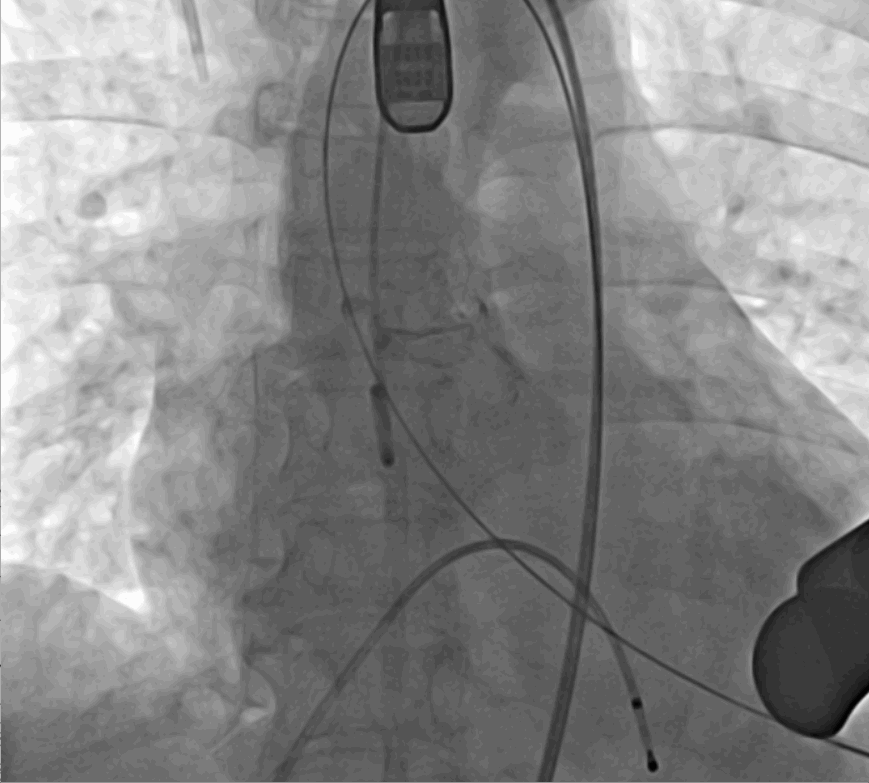

術中釋放定位鍵后DSA影像圖